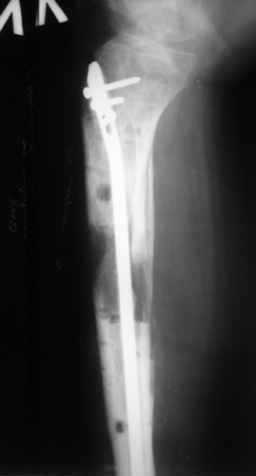

Ситуация пока на следующем этапе:

Больному выполнена резекция малоберцовой кости, ВХО раны, сближение отломков. Резекция м\б через отдельный разрез. После ВХО компрессия в аппарате, края раны сближены наводящими швами (без натяжения).

В случае гладкого заживления раны, при условии положительного решения вопроса с металлом, планируем перемонтаж аппарата Илизарова, дополнительную резекцию дистального отломка, выведение полокости голеностопного сустава в правильное положение (см. боковую Р-грамму), одномоментно остеотомия большеберцовой кости. После восстановления длинны голени, по всей видимости, артродез голеностопного сустава.

Рентгенограммы прилагаются. Фото местного статуса выложу в ближайшее время.

Уважаемые коллеги! В принципе у Вас есть еще время решить дальнейшую тактику, но у меня вопрос: почему остеотомия малоберцовой кости произведена на уровне перелома б/б кости?

Мне кажется надо было произвести косую остетомию в В/з м/б кости!

Так как в данном случае зона вилки ГСС ослаблена (нестабильна), а она вам нужна будет при артродезирования и еще дистальный отломок м/б кости не фиксирована спицей? при билокальном остеосинтезе особенно во время дистракции будут проблемы в данной зоне!

Мы обычно не фиксируем малоберцовую кость. Просто стараемся сопоставить ее концы за счет хорошей репозиции. В представленном случае имеется некоторое смещение дистальных фрагментов кнаружи, и, как мне кажется, ротация их вместе со стопой кнутри (ротация хорошо заметна на прямом снимке по форме таранной кости и на боковом по соотношению отломков малоберцовой). Если это действительно так, то это несложно сейчас постепенно устранить в аппарате. И тогда концы малоберцовой кости будут находиться поближе друг к другу.